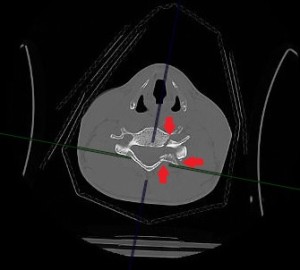

Перелом поперечного отростка, корня дужки и дуги пятого шейного позвонка – выделены стрелками

Зона перелома выделена красным цветом и Перелом поперечного отростка, корня дужки и дуги пятого шейного позвонка – выделены стрелками

В ходе диагностики была выявлена тяжелая комплексная травма шейного отдела позвоночника. Врачи обнаружили множественные переломы пятого и шестого шейных позвонков, вывих пятого позвонка, разрыв межпозвонкового диска с образованием грыжи, сдавливающей спинной мозг.